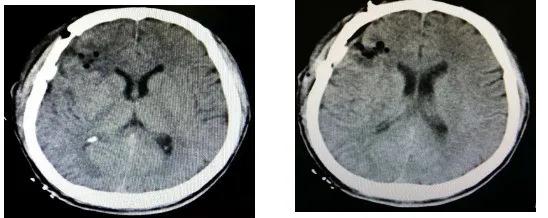

术后患者意识很快清醒,肢体活动自如,ICU观察1天后转入外科治疗,在外科医护人员细致入微的治疗护理下,患者病情逐渐好转,术后9天痊愈出院,出院时患者情绪稳定,生活基本能够自理,家属特别满意,万分感谢外科医护人员。

(术后复查头颅CT影像)